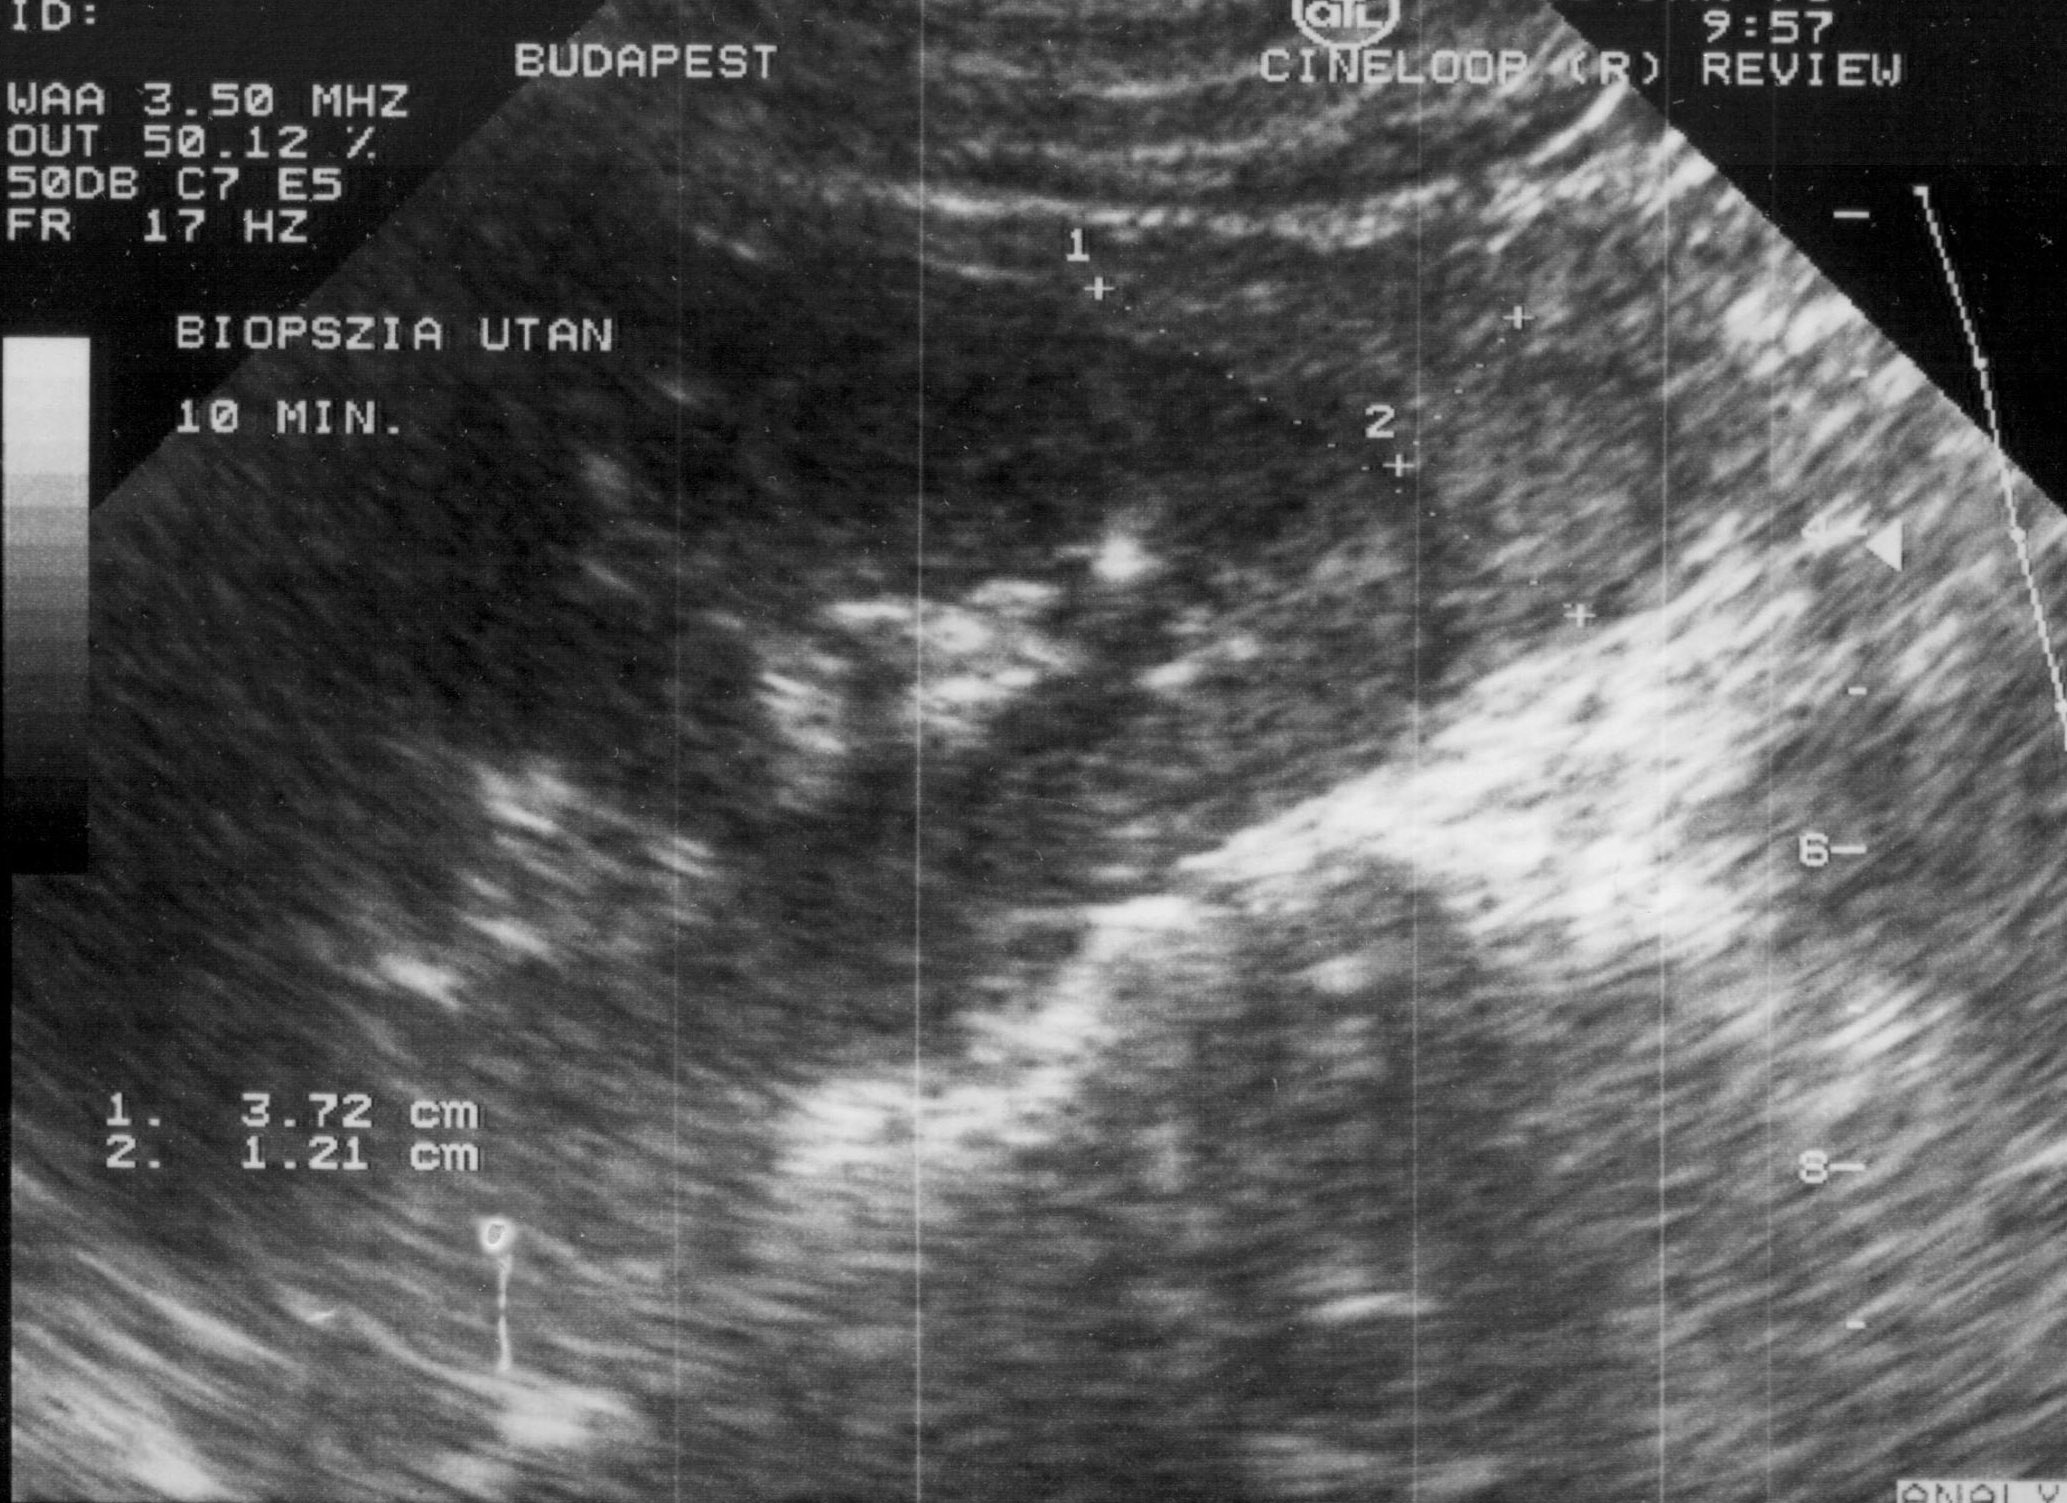

- Hemorrhage (subcapsular (figure 12.), parenchymal, intraabdominal (figure 13.), intrathoracic, pseudoaneurysm),

Image

Figure 12. – US guided renal biopsy, subcapsular hemorrhage (5 minute control)